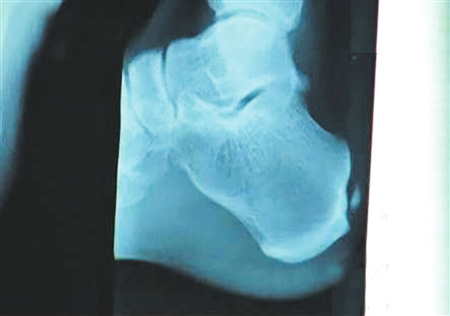

手術(shù)要取出的鈣化物就在這里。 圖片來源:華西都市報